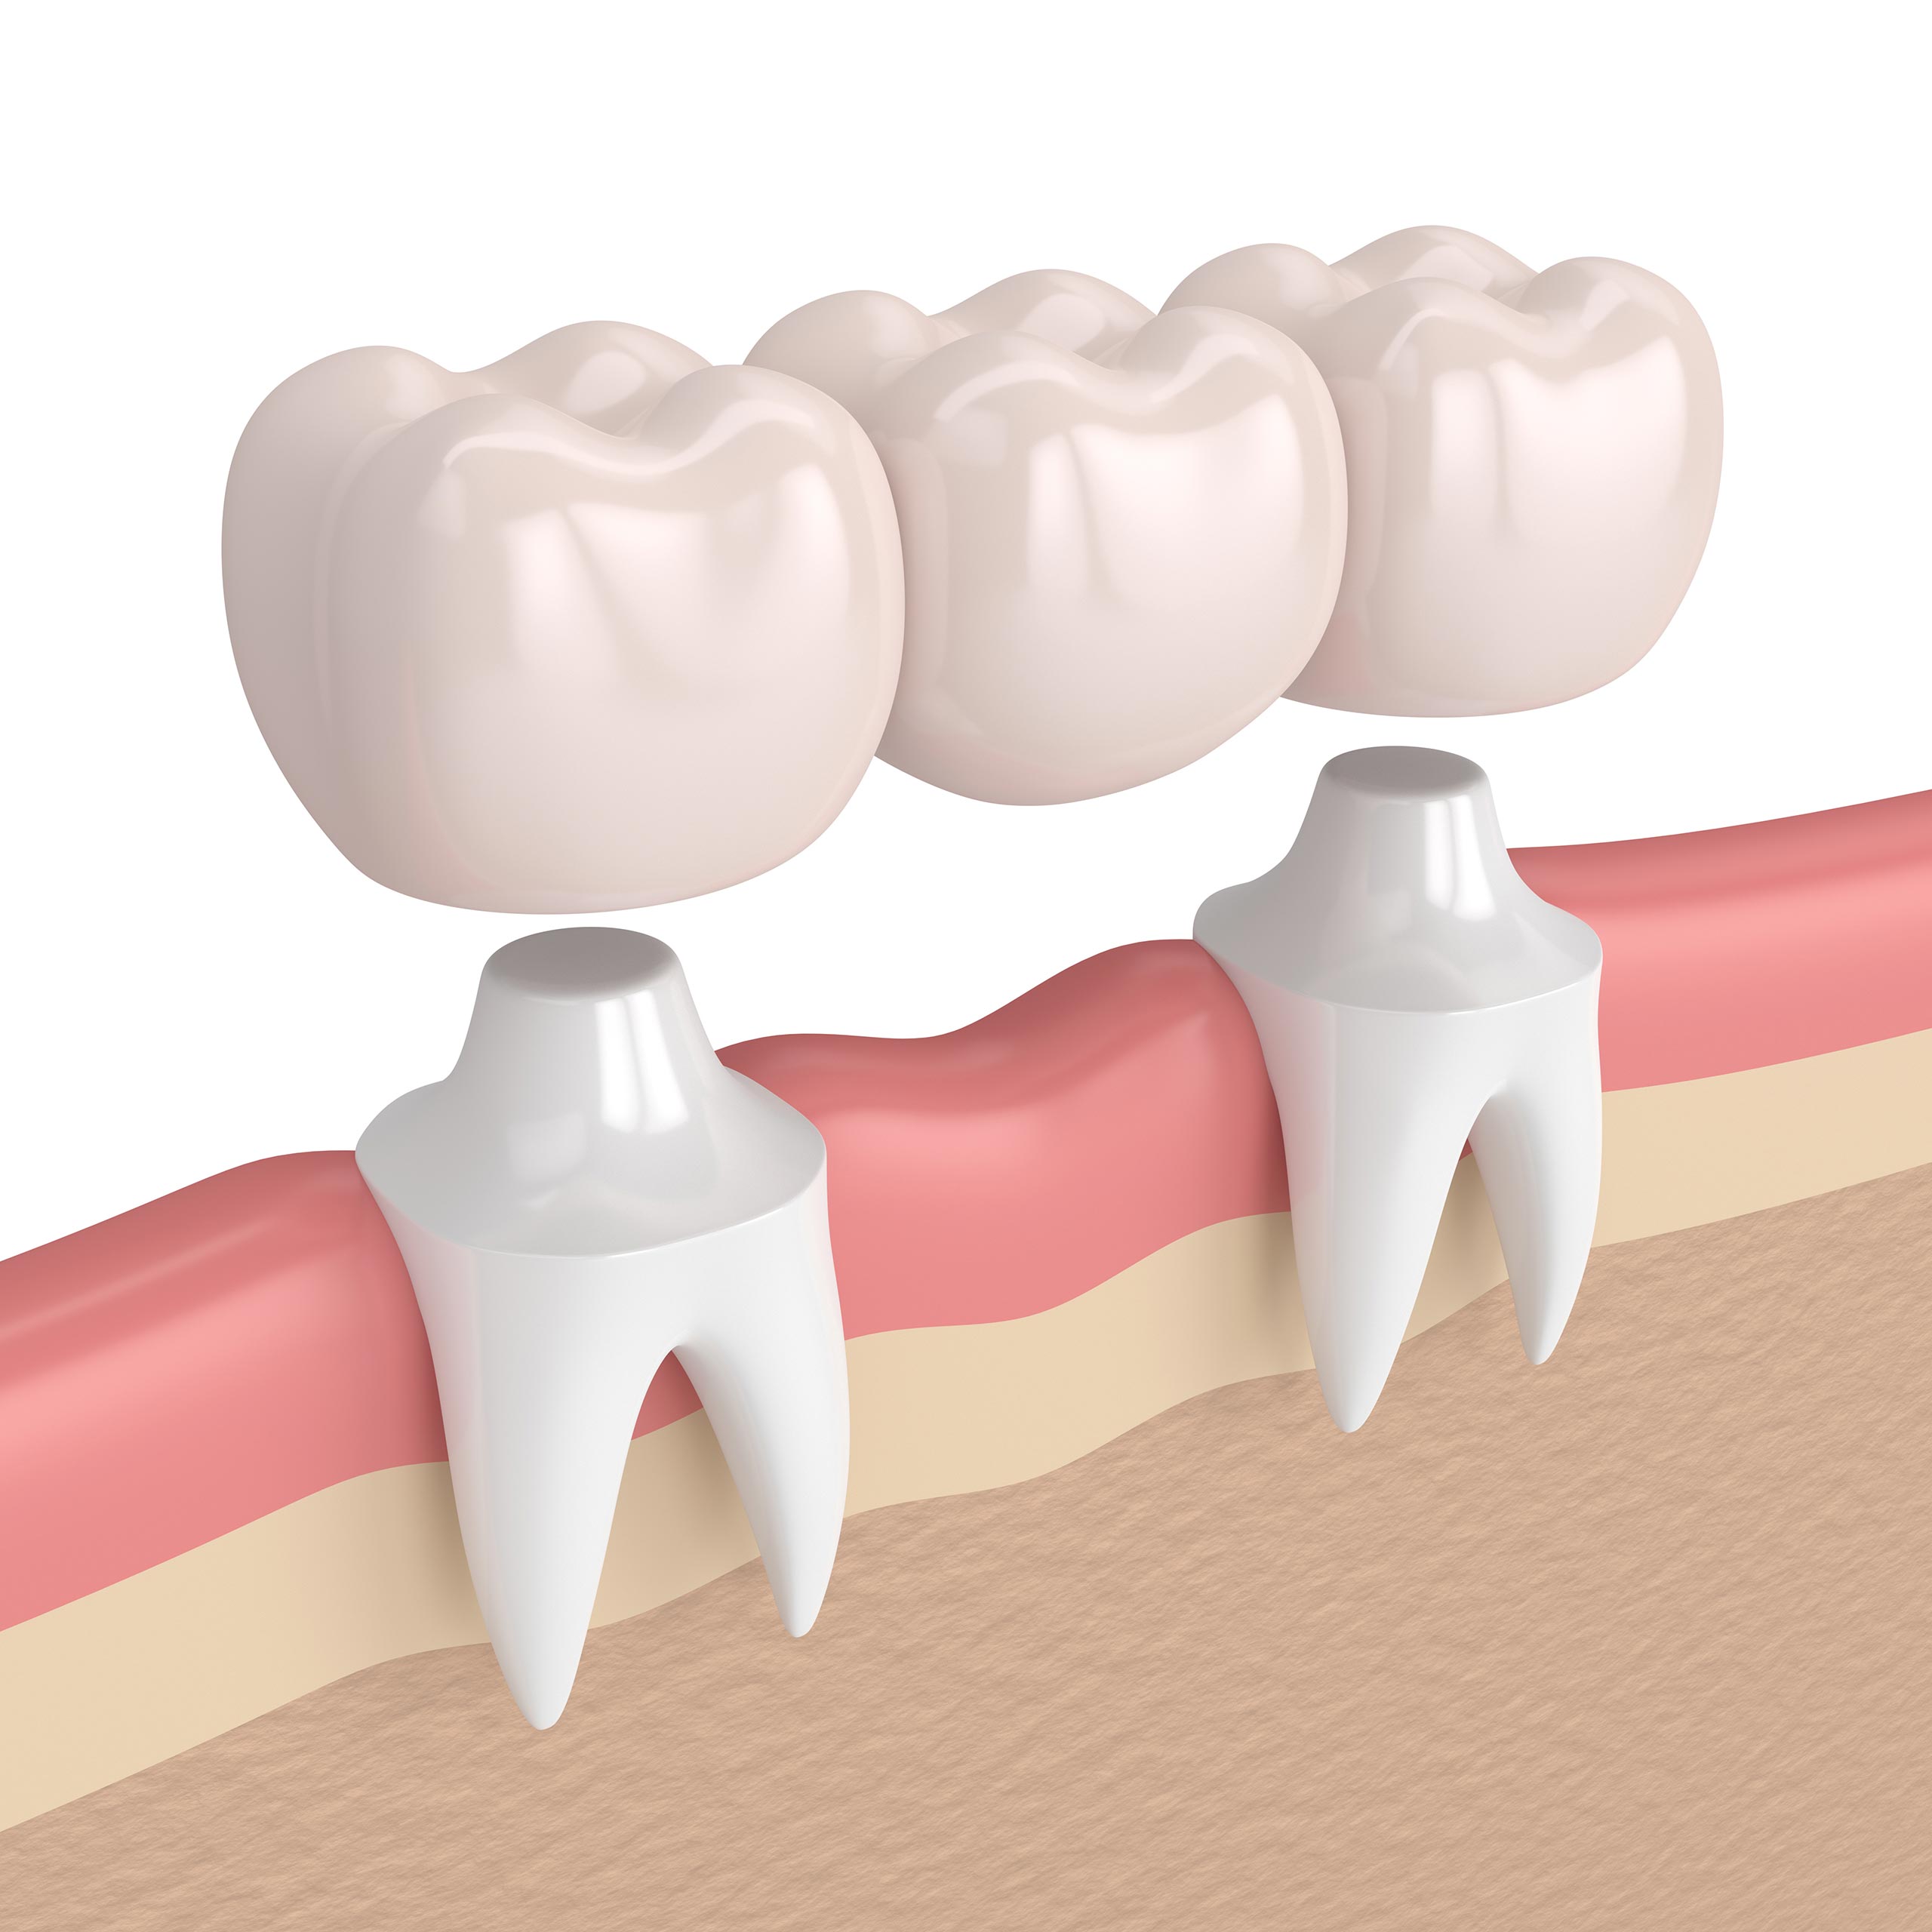

Bridges | All Smiles Dental Practice Ltd

www.allsmiles.co.kebridges

www.allsmiles.co.kebridges

Dental Bridge | Tooth Crowns & Bridges Auckland | CM Dental

cmdental.co.nzbridge dental bridges tooth nz crowns work

cmdental.co.nzbridge dental bridges tooth nz crowns work